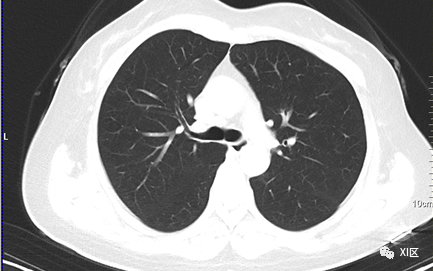

文章插图

图片源自网络 图文无关